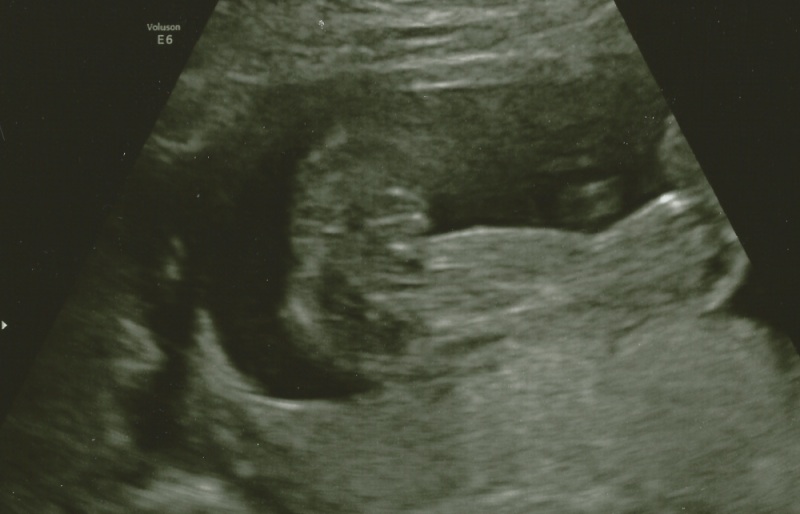

I'd say that's a girl:) did they say?

Thank you. The tech said that she thinks it could be a girl, but not to hold her to it. Was just wondering what the experts on here think!

girl

Looks like a girl to me!

Looks like a girl!

It looks like a girl to me. Gongrats!

Pink I think

I think girl too x